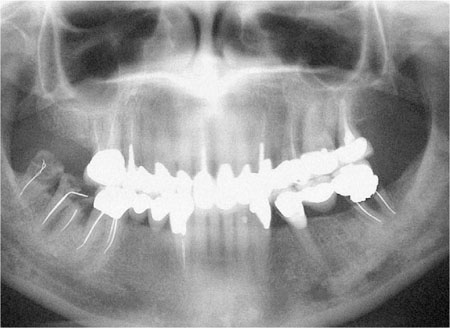

Studies on the failure of indirect restorations indicate that the commonest cause of failure is secondary caries as diagnosed clinically. Other causes include various forms of mechanical breakdown and failure, together with unacceptable appearance and endodontic and periodontic complications.

Caries remains the most important disease that affects teeth. It is responsible for most directly placed restorations and their subsequent replacements. Ultimately, when direct restorations are contraindicated, indirect restorations are required, but typically these will not be permanent and will fail because of caries. This is ironic given that dental caries is a preventable disease.

Failures such as those illustrated in Fig 1-4 are preventable. It is important that we learn from such failures, by ensuring that operative dentistry is preventively driven.

Fig 1-4 Dental panoramic tomogram of a patient with an extensively restored dentition; including multiple indirect restorations. Failure of many of the restorations has been caused by caries, some have been lost (LR7 and 8), and some have been repaired (LL5).

Once caries has been stabilised the next phase of the treatment can be considered, including decisions as to which teeth should be restored. Some teeth may need extraction or root canal treatment. Initially, temporary restorations should be replaced with simple restorations. Before considering costly and time consuming indirect restorations, further assessment is required to ensure compliance with oral hygiene procedures and to assess caries activity. In this way, the success of primary preventive measures are reassessed, and only if they have been successful should indirect restorations be considered. If in doubt, further preventive advice is indicated, together with repeat follow-up reviews. Failure to do this is likely to result in a disastrous outcome as illustrated in Fig 1-4.